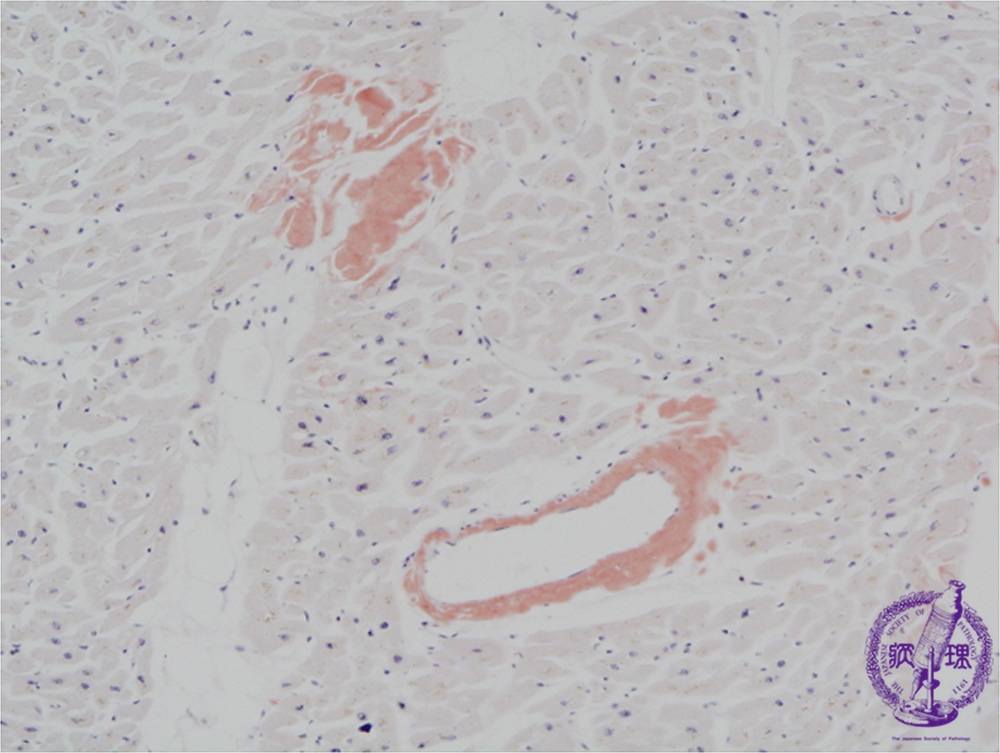

Microscopic image (Congo-red stain, low power view): There are small deposits of amorphous substance on HE staining composed of amyloid as demonstrated by Congo red stain (arrow). Amyloid deposition is confirmed by polarized light microscopy, which shows focal apple green birefringence.